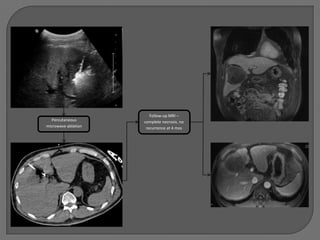

TACE #3 11/18/2010

75 mg doxorubicin on

LC beads to R phrenic

and R hepatic arteries

MRI 10/25/2010:

Intrahepatic recurrence

MRI 12/20/2010: Minimal residual tumor

Successful OLT 1/22/2011 (1 year after first

intervention)

Now almost 1 year s/p OLT, doing well

without recurrence

YO

58 y/o male

Hepatitis B and C and HIV

Abdominal pain prompted CT

7 cm biopsy-proven HCC

Not a surgical or transplant candidate

Referred for locoregional therapy

MRI 1 month later –

100 mg doxorubicin on      mass mostly

LC beads           devascularized

Follow-up MRI –

Percutaneous       complete necrosis, no

microwave ablation    recurrence at 4 mos